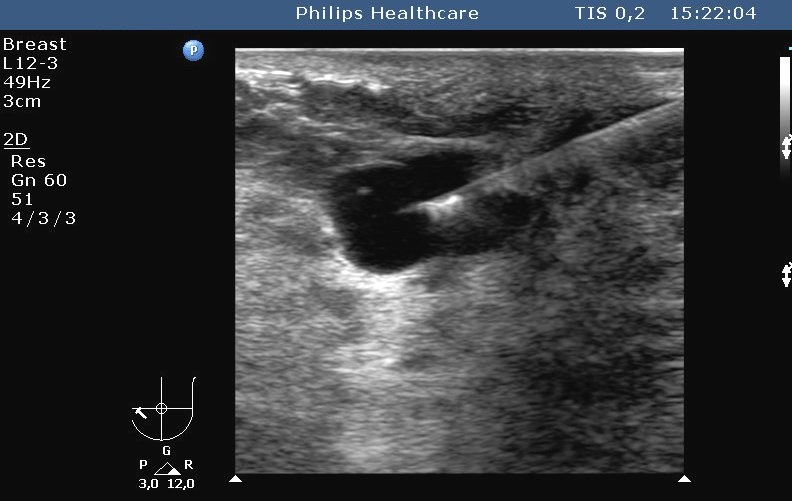

19.2.2.1 US guiding

Nowadays it is the most commonly used method. Both superficial (figure 3.) and deep (figure 4.) lesions can be biopsied.

Image

Figure 3. – US guided, fine needle aspiration biopsy (breast cyst puncture)